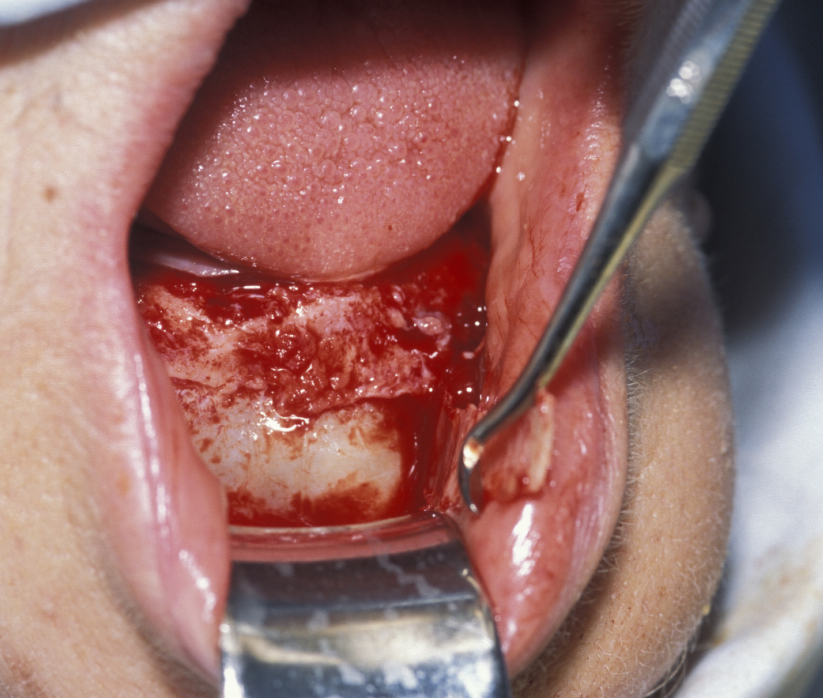

Figure 8: The cyst lining is retained and in continuity with oral epithelium externalizing the cyst.

Figure 9: The defect is packed with iodoform gauze. This allows gradual resolution of the defect as new bone displaces the cavity lining.